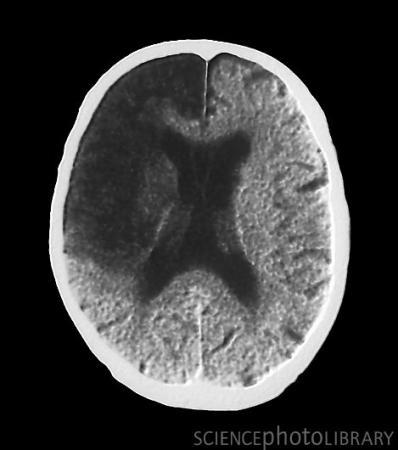

脑中风CT扫描(图)

中风是一种急性脑血管病,发病时患者大脑血液供应中断,使得脑神经细胞无法获得氧气和养分而死亡,致使大脑认知功能的丧失,造成失语、瘫痪等症状。该病致残率和致死率都很高,且容易复发,是威胁人类健康的重要杀手。在英国中风是第三大致死疾病。